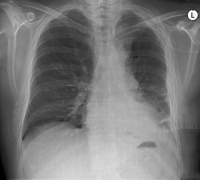

Thoraxröntgen

Abbildung 2: Postoperatives Thoraxröntgen (7.po) vor Entlassung